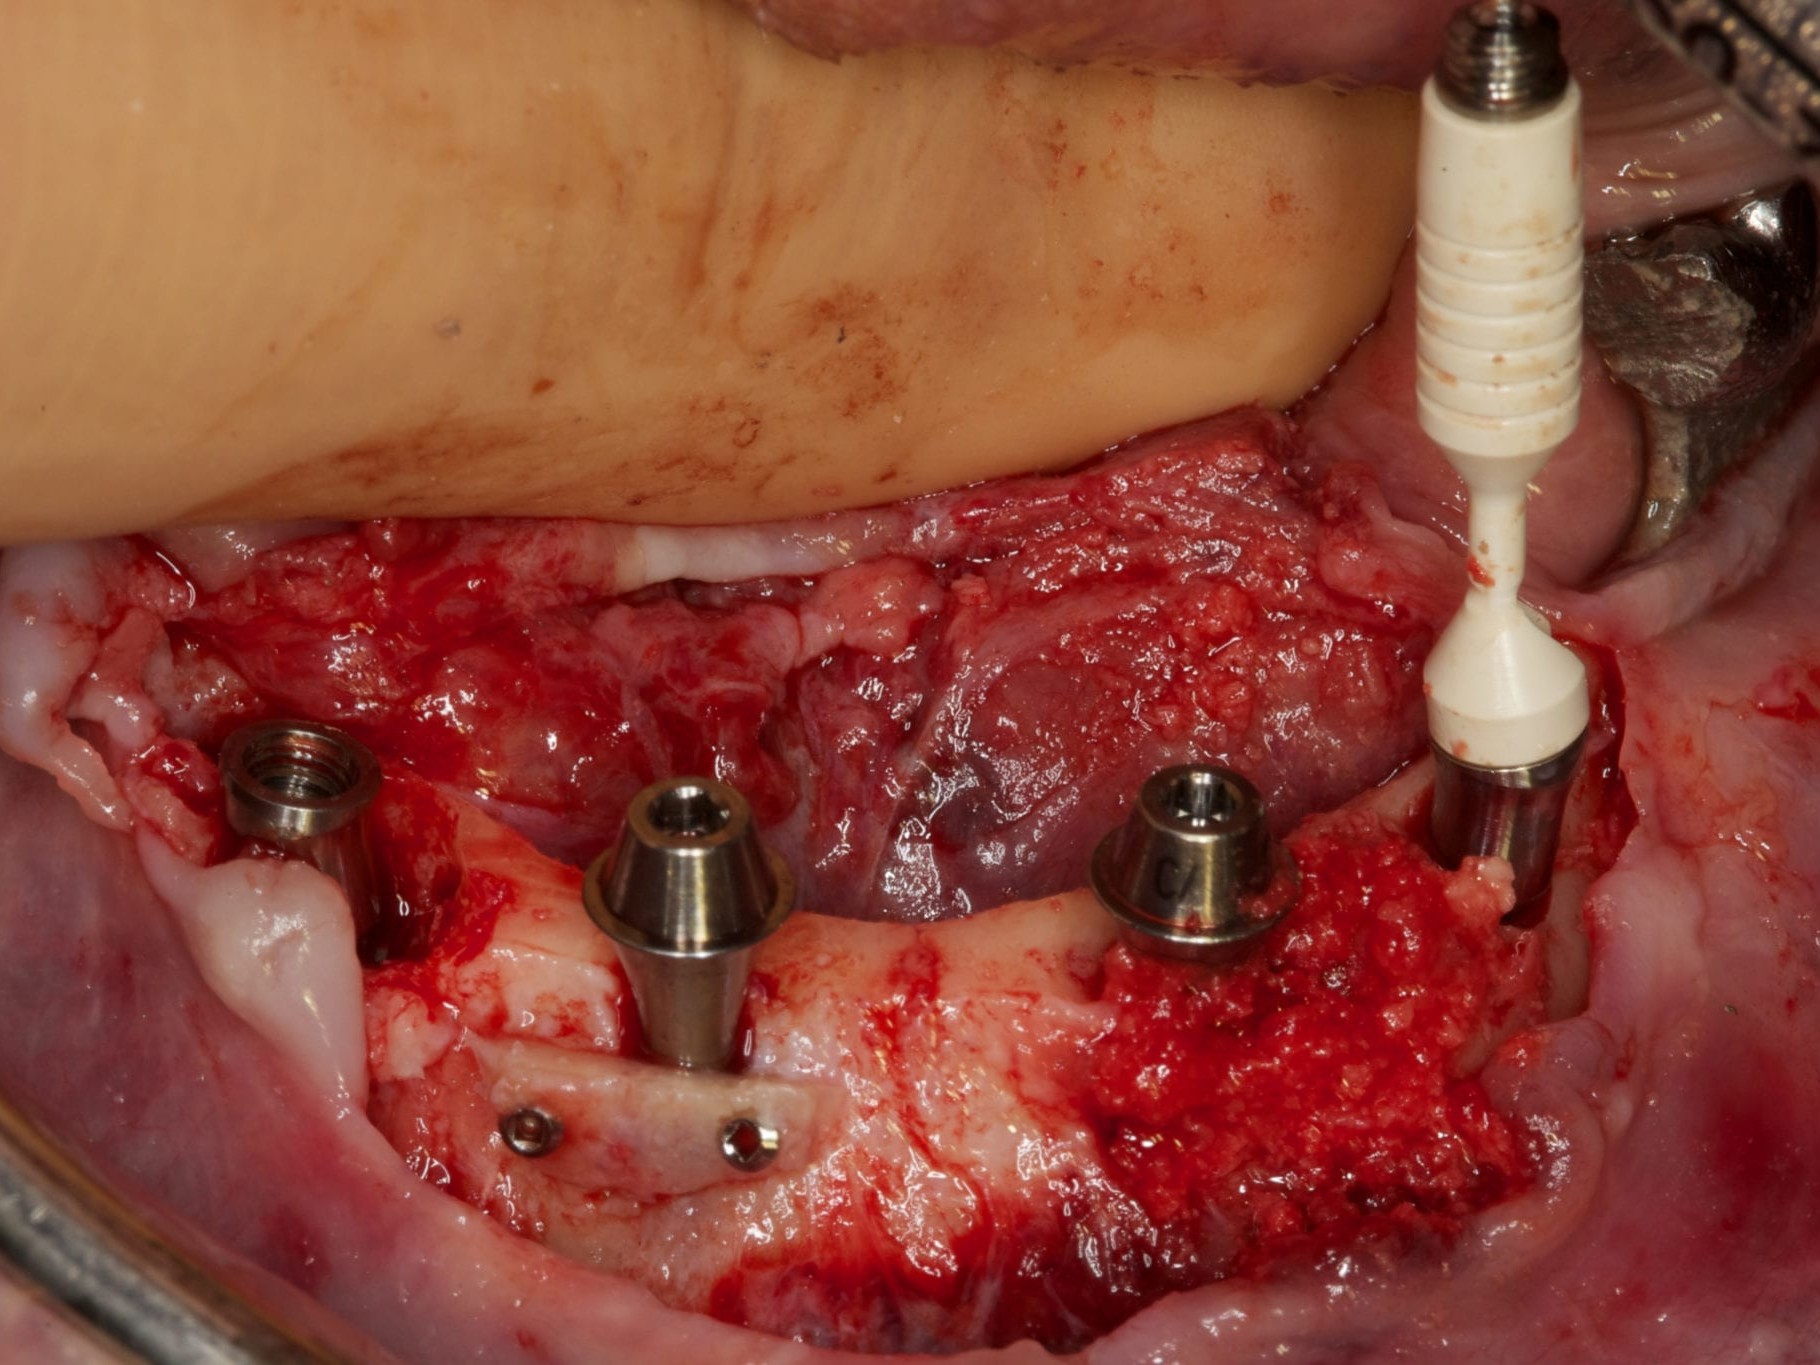

Für die Allgemeinanästhesie erfolgte zunächst die zusätzliche Gabe eines typischen Infiltrationsanästhetikums. Intravenös wurde unmittelbar präoperativ das Antibiotikum Clindamycin 600 mg gegeben. Abbildung 7 zeigt die klinische Ausgangssituation linksseitig. Nach der vorsichtigen Durchtrennung der Brückenkonstruktion (Abb. 8) jeweils vor der Krone auf den Blattimplantaten und Entfernung der nicht erhaltungswürdigen Zähne 44 bis 33 samt ihrer Überkronung (Abb. 9) wurde der Mukoperiostlappen vestibulär wie lingual passend zur erstellten Schablone präpariert und die Bohrschablone in ihrer finalen Lage eingebracht (Abb. 10). Zunächst erfolgte die Insertion der angulierten Implantate Ankylos ® C/X-Implantate (Durchmesser 3,5 mm) der Länge 14 mm in regio 034 (Abb. 11 und 12) und 044. Danach wurden in den Positionen 032 und 042 jeweils ein weiteres Ankylos ® C/X –A-Implantat mit gleicher Länge und Durchmesser inseriert (Abb. 13). Sämtliche entfernten Knochenpartikel und auch Bohrspäne wurden akribisch asserviert. In den Positionen 032 und 042 wurden Ankylos ® Balance Basisaufbauten C/ (GH 3,0 / Ø 5,5 mm, Kopfhöhe 2,4 mm) mit 15 N/cm eingeschraubt. Anschließend hat der Zahntechniker mittels der Ankylos ® Modellierhilfskappenfür den Balance Basisaufbau Retentionskappen hergestellt, die mit 25 N/cm eingebracht wurden (Abb. 14). Am Implantat regio 042 wurde der Knochen in Schalentechnik nach vestibulär aufgebaut (Abb. 15)⁹,¹⁰. Im nächsten Schritt haben wir die angulierten Ankylos ® Balance Basisaufbauten C (nicht indexierte Abutments) in Regio 034 und 044 (GH 3,0, A30 / Ø 4,2 mm, Kopfhöhe 1,3 mm) ausgerichtet und ihren spezifischen Vorgaben entsprechend eingebracht (Abb. 16). Nachdem sich alle erforderlichen prothetischen Implantatbauteile in situ befanden (Abb. 17), erfolgte die Überprüfung und geringfügige Anpassung des im Vorfeld digital erstellten Sofortprovisoriums. Im Anschluss wurden die leeren Alveolen und Knochendefekte mit dem gewonnenen autologen partikulären Material aufgefüllt. Dann erfolgte der typische Naht-Wund-Verschluss mit Einzelknopfnähten eines resorbierbaren Nahtmaterials (Abb. 18). Nachdem die Patientin aus der Vollnarkose erwacht war und ihre motorischen Fähigkeiten wiedererlangt hatte, wurde das Sofortprovisorium eingesetzt und in Okklusion gebracht. In dieser Position wurden die Retentionskappen über ein selbsthärtendes fluoreszierendes kaltpolymerisierendes Paste-Kartuschensystem fixiert. Anschließend erfolgte die extraorale Versäuberung des Interimszahnersatzes. Nach Refixierung des Sofortprovisoriums in der Mundhöhle (Abb. 19 und 20) und dem Verschluss der Schraubenkanäle mit Kunststoff erfolgte die radiologische Kontrolluntersuchung (Abb. 21).